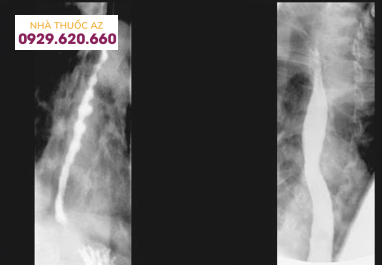

4.1. Hình ảnh X quang thực quản cản quang bình thường

Thực quản bình thường có bờ rõ nét, các nếp niêm mạc chạy song song nhau, được chia làm ba đoạn:

Đoạn cổ ngắn.Đoạn ngực dài nhất, nằm sát bờ sau tim, có hai dấu ấn của động mạch chủ và phế quản gốc trái đè vào.Đoạn bụng rất ngắn, sau khi chui qua lỗ hoành và kết thúc bởi tâm vị, đổ vào mặt sau – trong phình vị lớn dạ dày và tạo với phần này một góc nhọn đó là góc His, có chức năng chống trào ngược dạ dày – thực quản.

Hình 4: Hình ảnh X quang thực quản cản quang bình thường